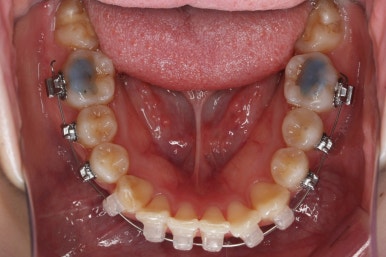

위 사진은 연산동교정치과 처음 내원하셨을 때의 입안 모습입니다. 몇 가지 모습이 관찰됩니다.

치아가 삐뚤삐뚤합니다.

위~아래 앞니가 많이 겹쳐서 아랫니가 많이 모이지 않는 "과개교합" 입니다.

앞니가 앞으로 뻐뜨러져 있습니다.